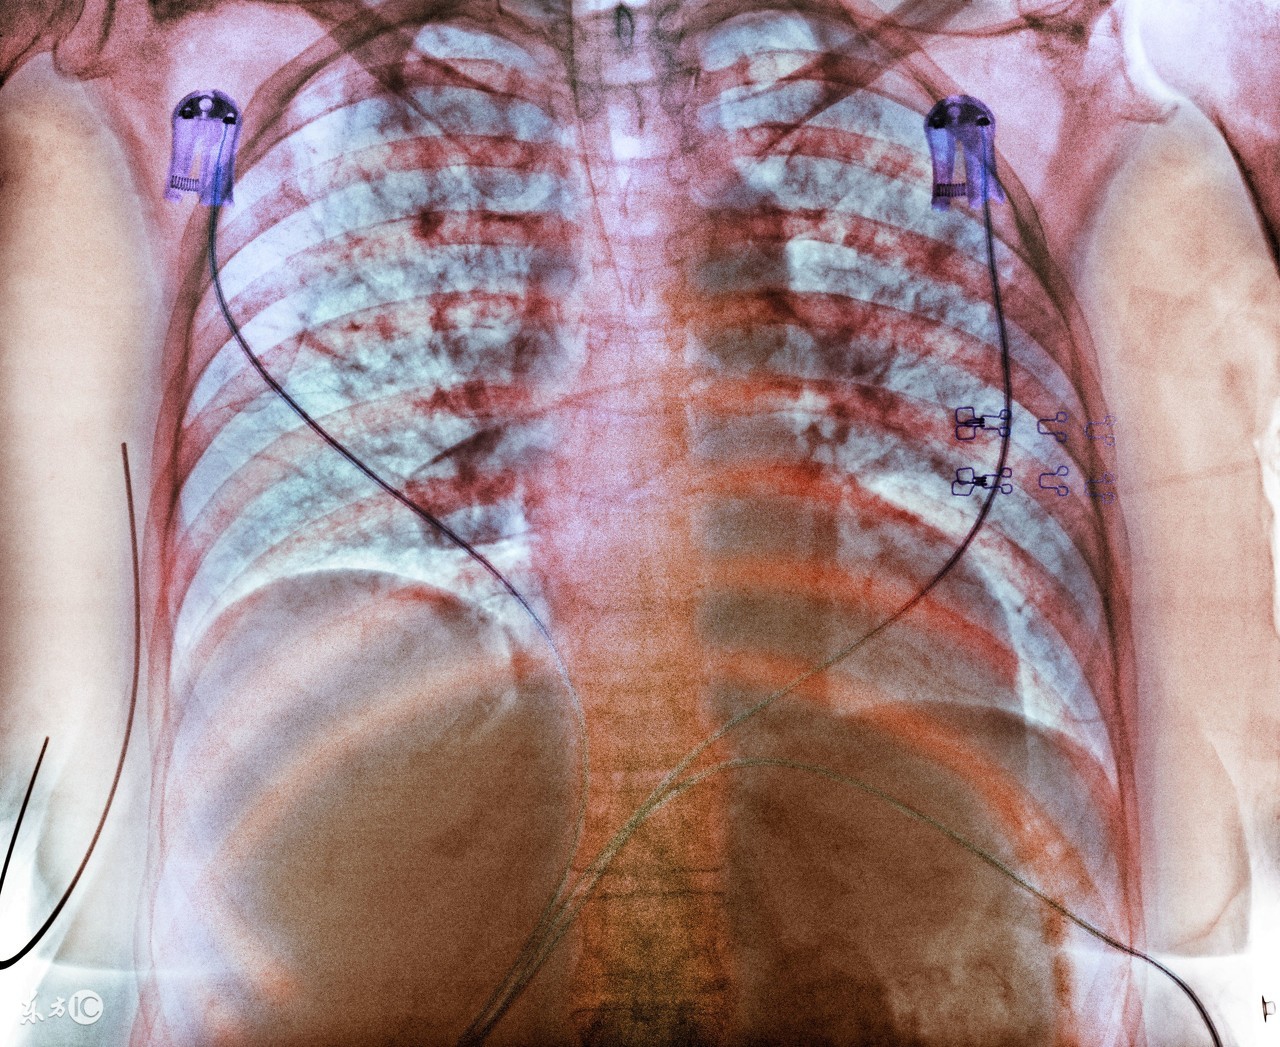

很多肺结核患者在确诊之后,就要马上接受治疗。其实,在临床上,治疗肺结核的方法有很多,很多早期的患者会选择药物治疗,严重的患者就要接受临床治疗了。那么,中医怎样治疗肺结核疾病?其实,治疗方法是根据患者的病情所决定的,中医治疗对于患者的身体损害是很小的。